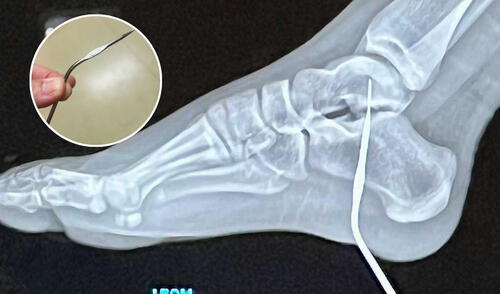

El hospital en California al que fue llevada Georgia fue el escenario de una sorpresa para los médicos que atendieron su caso. Después de realizarle una radiografía, los médicos confirmaron que la aguja había quedado incrustada profundamente, pero afortunadamente no había afectado estructuras vitales como huesos, nervios o músculos. "Fue un accidente extremadamente inusual", comentó Ashley.

Después del tratamiento inicial, Georgia fue sedada levemente para permitir a los médicos retirar la aguja de su pie sin causar más trauma. Afortunadamente, la niña no necesitará un largo proceso de rehabilitación, ya que no sufrió daños en estructuras internas del pie. Para su sorpresa, se espera que recupere su movilidad en pocas semanas. Georgia, quien es aficionada al rugby y al baloncesto, inicialmente temía que el accidente pudiera poner en riesgo su regreso a los deportes. Sin embargo, los especialistas le aseguraron que solo necesitará paciencia y gradualidad para retomar sus actividades deportivas.